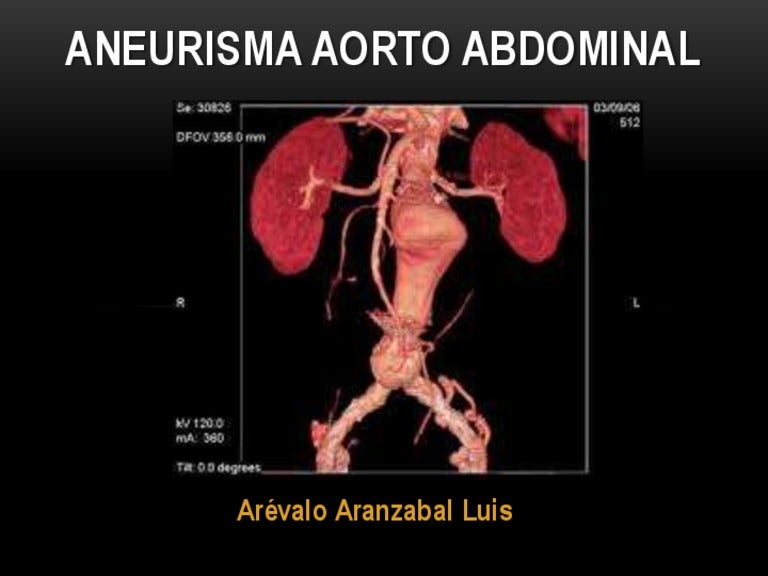

Un aneurisma aórtico abdominal es un agrandamiento de la parte baja de la aorta que se extiende a.

aneurisma de la aorta abdominal La aorta va desde el corazón hasta el. Recibe sangre con gran contenido en oxígeno. Cirugía vascularrupturas de aneurisma de la aorta abdominal: La cirugía de reparación abierta de aneurisma aórtico abdominal (aaa) se realiza para arreglar una parte dilatada de la aorta. Si tienes un aneurisma de la aorta abdominal en expansión, podrías notar lo siguiente: La incidencia de aaai en. En este artículo examen físico pruebas de detección y de diagnóstico ¿quiénes deben someterse a un examen de detección de aneurisma de aorta torácica? Los aneurismas aórticos aneurismas aórticos la aorta, que mide alrededor de 2,5 cm de calibre o diámetro, es la arteria más grande del cuerpo.

Aorta Abdominal / Abdominal Aortic Aneurysm Cardiovascular